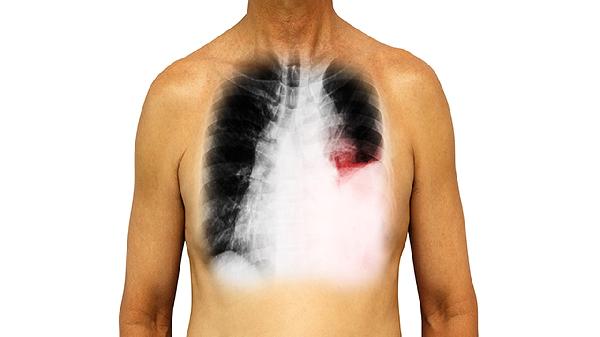

肺微小结节的治疗方法主要有定期随访观察、生活方式干预、药物治疗、介入治疗和手术治疗。肺微小结节通常指直径小于8毫米的结节,多数为良性,可能与既往感染、炎症或粉尘暴露等因素有关。